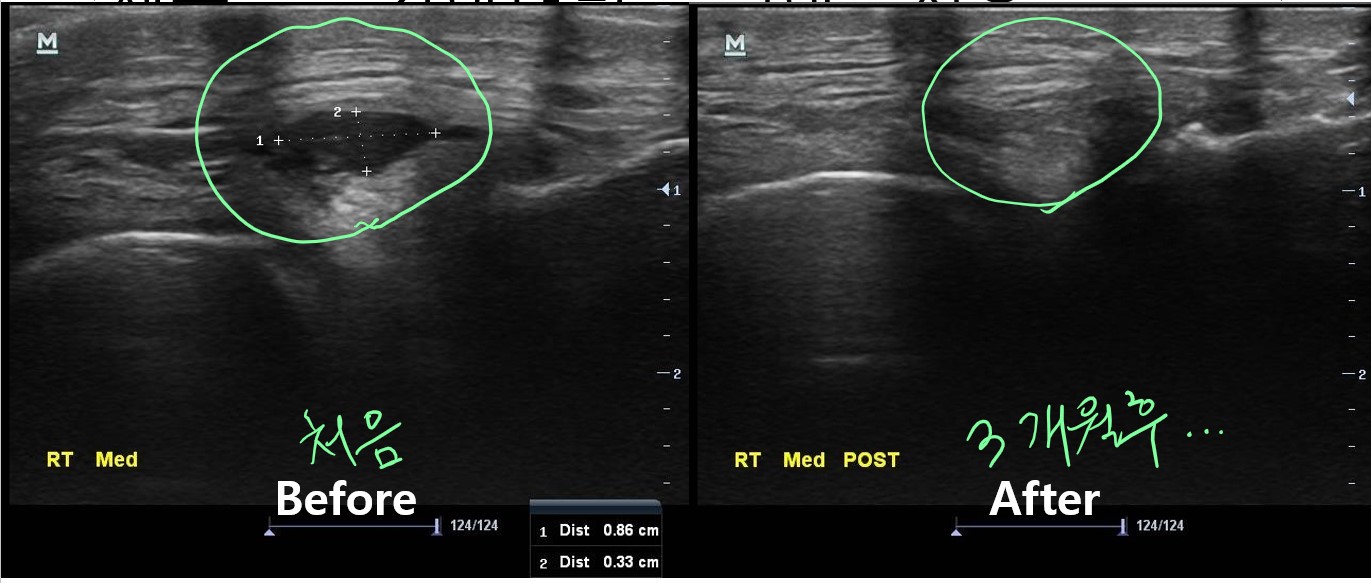

이 환자분의 진짜 문제는 초음파 검사에서 발견되었습니다.

나 : 내측반월판 연골 부위에 물혹이 하나 생겨있습니다.

나 : 네 결절종이라고 하는 건데요... 무릎을 굽히실때 이게 주변 조직을 누르면서 통증이 발생한듯 합니다.

나 : 초음파 보면서 주사기로 물혹속 내용물을 제거해봐야 할거 같습니다.

치료 후 3개월이 지난 현재, 이 환자분은 다행히 물혹이 재발되지 않아 큰 불편함없이 잘 지내고 있습니다. 아직 더 지켜보긴 해야 하지만요...